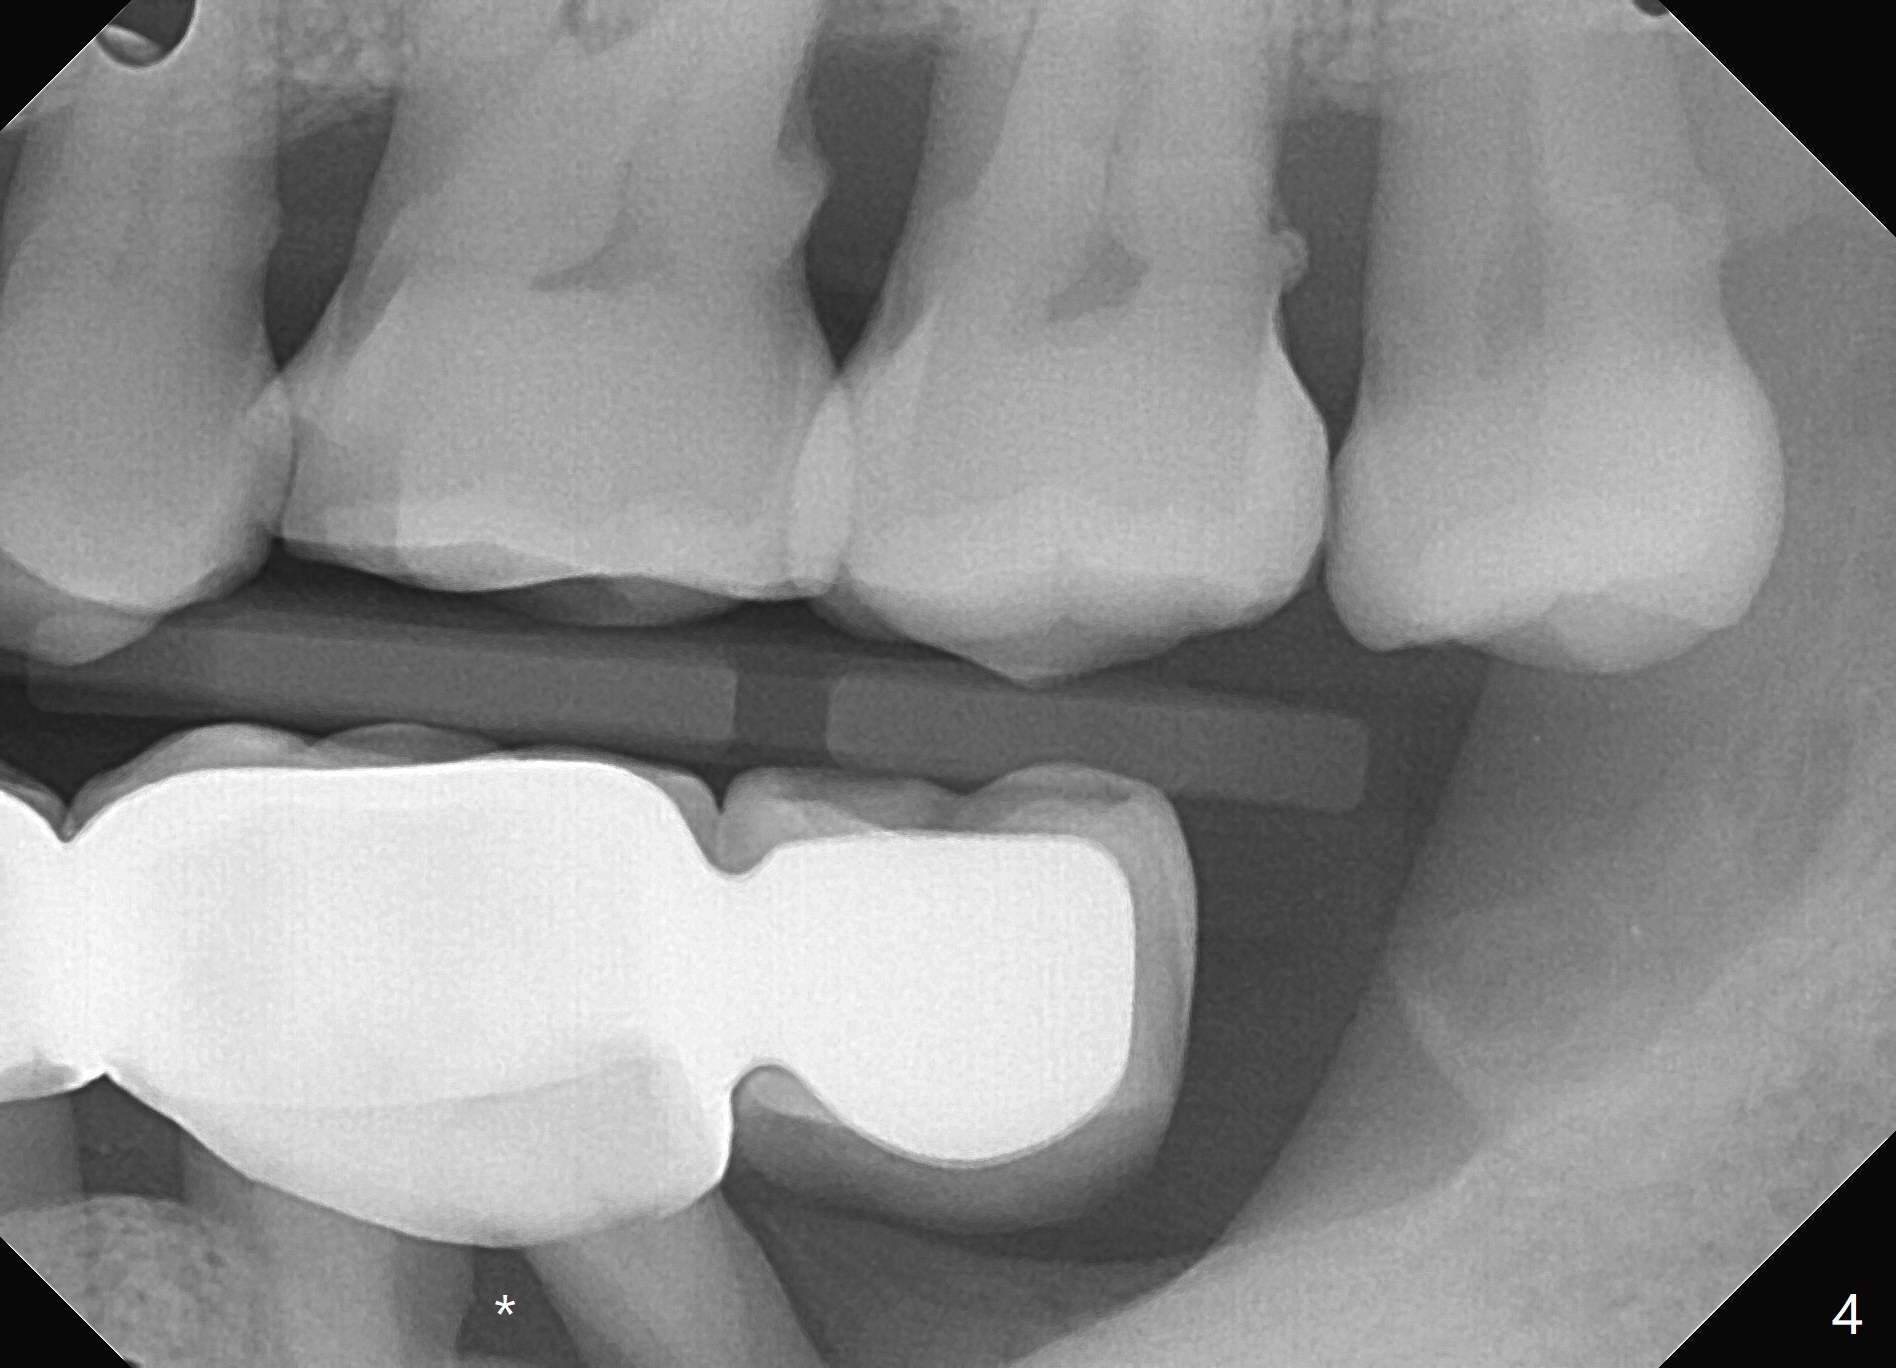

A 71 year old lady has issue with an upper bridge (#7-11, Fig.5-7). While one of the abutments (anchor teeth for FPD), #7, is "tender", the other (#11) fractures. Take Alginate impression (upper and lower) when she returns, pour models (no bubbles, 1 U, 2 L), and keep U Alginate for provisional. Section FPD at #7 and 9, take 12x9 cm CT with 2 cotton rolls and full arch impression for guide with bite registration. Prepare Endo Ice for #7 (tenderness). Tell the patient and her daughter that the lower left cantilever FPD is in bad shape, since the tooth #19 has large furca radiolucency (Fig.4 *). Next appointment should be scheduled for SRP (Fig.1-4).